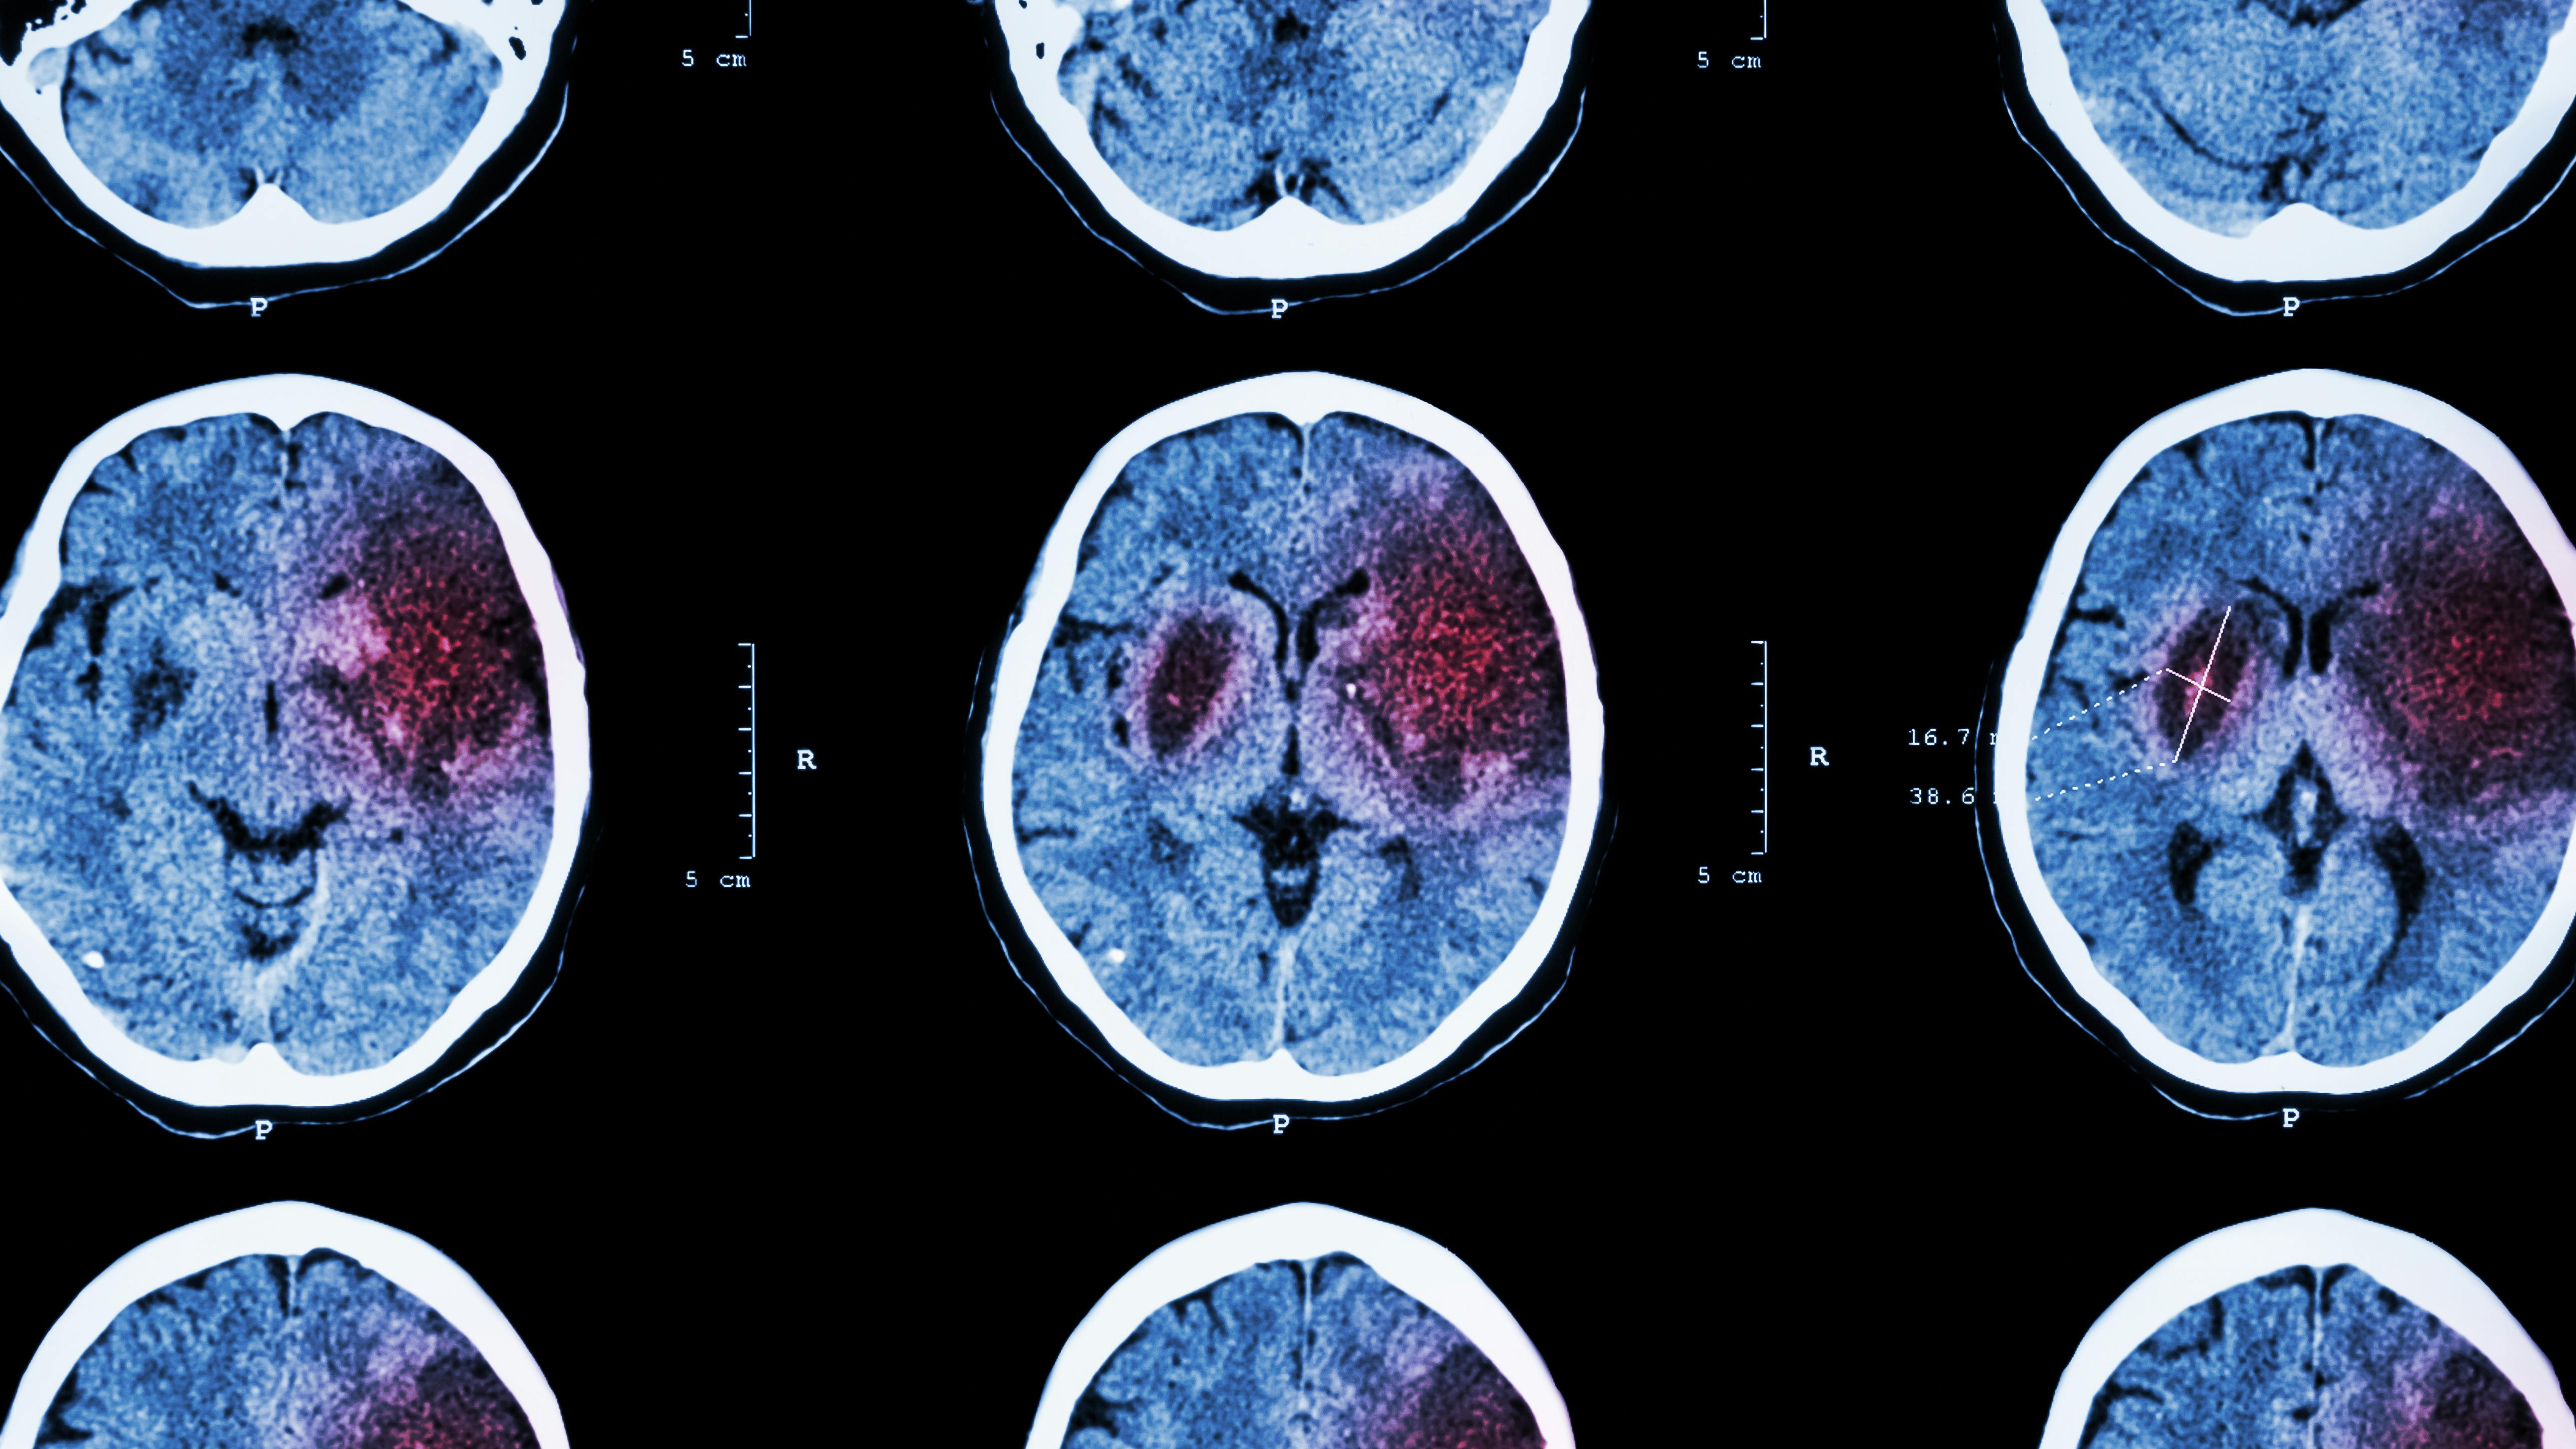

CIS refers to a subtype where the cause is not immediately identifiable despite comprehensive medical assessment. Ischemic strokes—which account for about 87% of all strokes—occur when an artery supplying blood to the brain is blocked, usually by a blood clot. In many cases, the underlying cause can be identified, such as atherosclerosis, cardiac arrhythmias (such as atrial fibrillation), or small vessel disease. Though less common overall, CIS is more characteristic in younger adults compared to older populations, where traditional risk factors such as hypertension, diabetes, and atherosclerosis are more prevalent.2